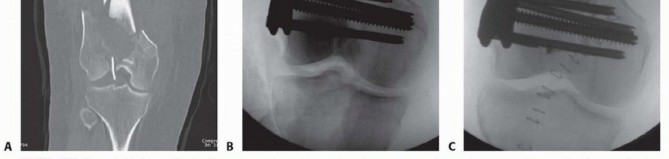

### FIG 4 • A,B. Coronal and sagittal CT angiography images showing intact femoral artery in a severely comminuted distal femur fracture (red arrows). Dedicated knee films should always be obtained in the assessment of distal femur fractures. Additionally, the entire femur, to include the hip and knee, should be imaged to look for possible extension and associated injuries and to allow for preoperative planning ( FIG 5). In cases of severe comminution, radiographs of the contralateral knee can aid in preoperative planning as well. A dedicated CT scan is an important adjunct to the preoperative planning when there is articular involvement ( FIG 6). Generally, extra-articular distal femur fractures do not require a CT scan. However, it has been shown that coronal fractures may be missed on plain films, and thus there is a low threshold for obtaining a CT scan for fractures of the distal femur. 11 If the fracture pattern warrants a temporary bridging external fixator, it is best to obtain the CT scan after placement of such a fixator for better definition. Coronal and sagittal reconstructions should be requested. Three-dimensional images can be created from most CT scans. This can also aid in the preoperative planning ( FIG 7A,B). Subtle sagittal plane rotational malalignment between condyles can be assessed ( FIG 7C). If associated soft tissue injury is suspected, such as ligamentous tears or tendon ruptures, then magnetic resonance imaging (MRI) may be indicated. Routine use of MRI, however, is not needed. ## DIFFERENTIAL DIAGNOSIS Proximal tibia fracture Femoral shaft fracture Septic knee Patella fracture Anterior cruciate ligament rupture Knee dislocation ## NONOPERATIVE MANAGEMENT There are few relative indications for nonoperative management of distal femur fractures: Poor overall medical condition Patient has severe comorbidities and is too sick for surgery. Patient has extremely poor bone stock. Spinal cord injury (paraplegia or quadriplegia) Some special situations may warrant nonoperative care on case-by-case basis. Nondisplaced or minimally displaced fracture Select gunshot wounds with incomplete fractures Extra-articular and stable Unreconstructable Lack of experience by the available surgeon or lack of equipment or appropriate facility to adequately treat the injury. Transfer is indicated in these situations; otherwise, nonoperative treatment may be the only option. There are several methods for nonoperative treatment. Skeletal traction Cast bracing Knee immobilizer Long-leg cast There are acceptable limits for nonoperative management: Seven degrees of varus or valgus Ten degrees of anterior or posterior angulation. A flexion deformity is less well tolerated than an extension deformity. Up to 1 to 1.5 cm of shortening Two to 3 mm of step-off at the joint surface 469

### FIG 6 • A. Axial CT image of patient in FIG 5A-C confirming the type B3 fracture of the medial femoral condyle. B. Axial CT image of the patient in FIG 5D-F. C-E. CT images of the patient in FIG 5G,H show the nondisplaced intercondylar split as well as the low lateral fracture line and extensive posterior metaphyseal comminution (type C2).